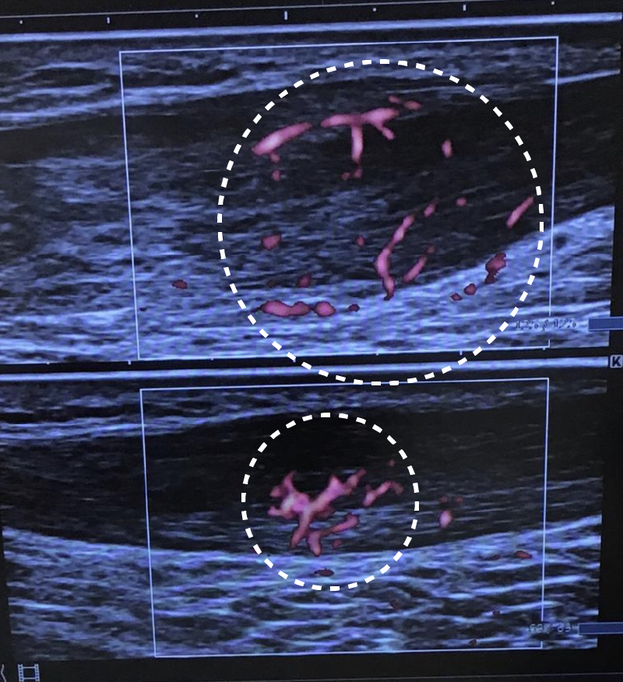

We use an echo to diagnose the affected area to quickly check whether your symptom is Achilles Tendinitis or not.

This is an ultrasonic echo image of Achilles Tendinitis. The white circled areas are where inflammation occurred and caused the pain.